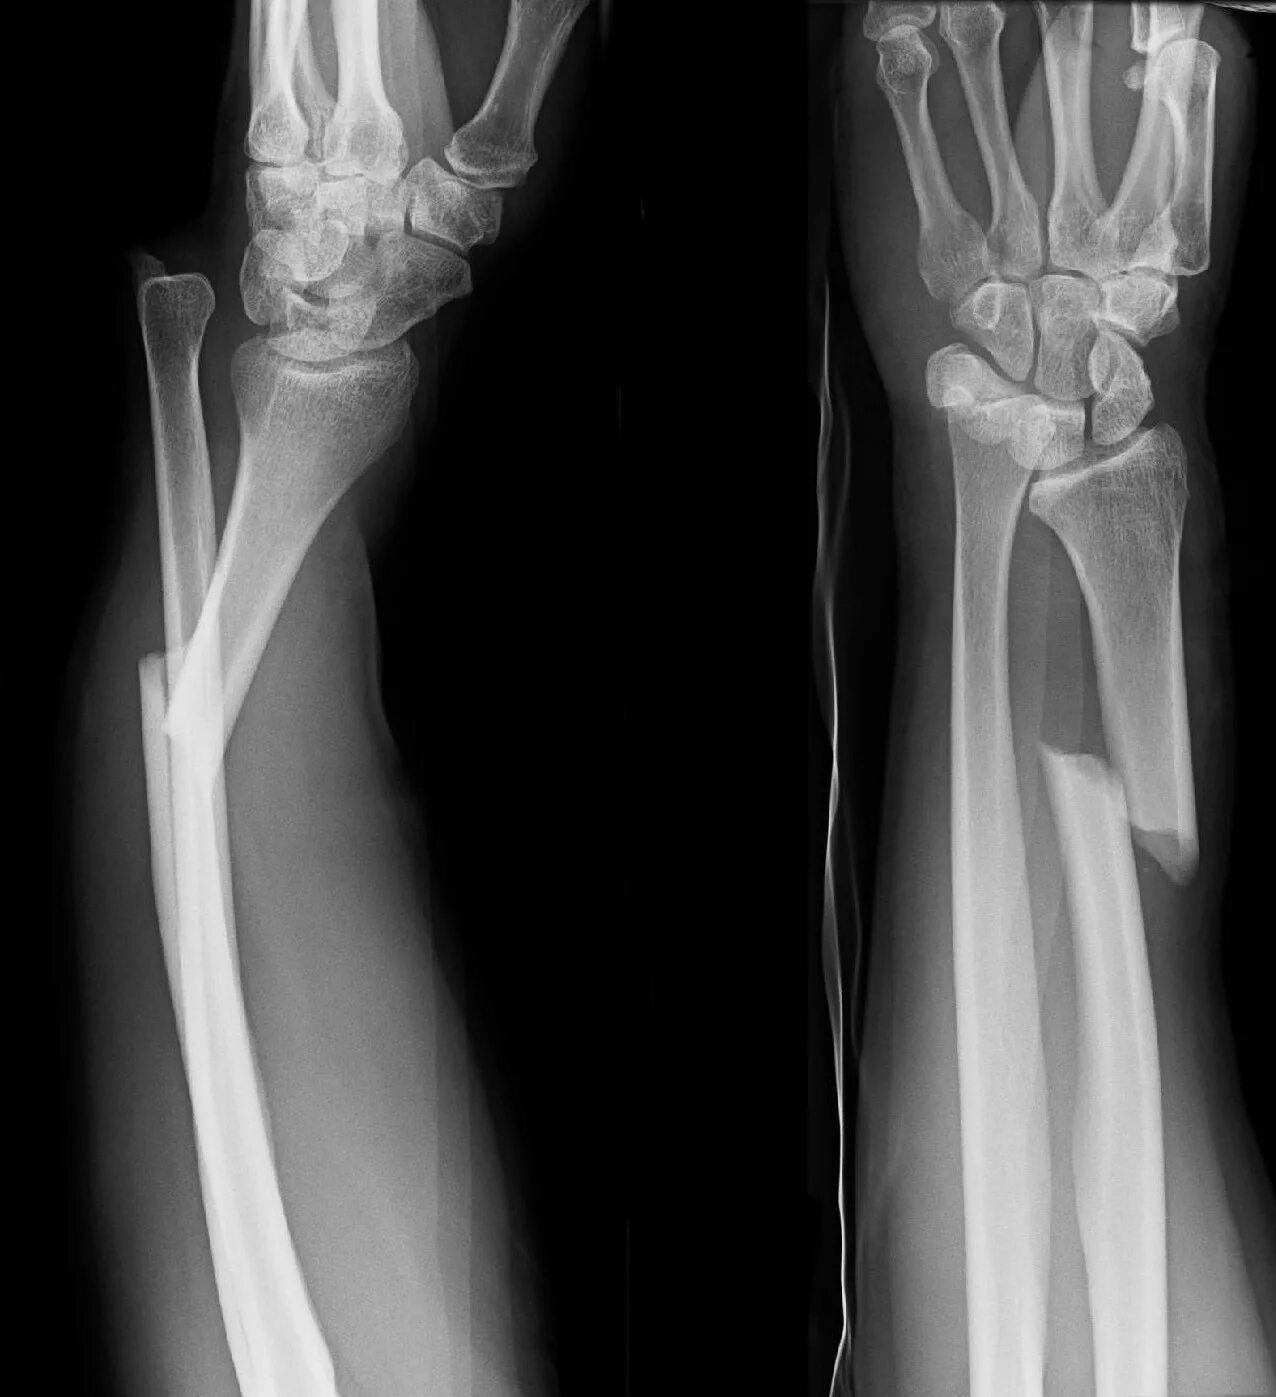

Fracture modeling